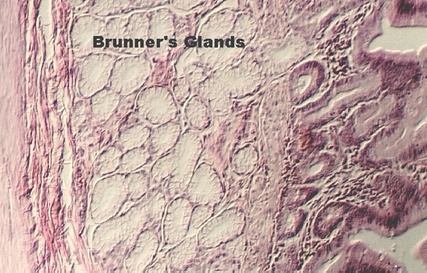

Crypt of Lieberkuhn and Brunner's glands

The base of the villus is called the CRYPT of LIEBERKUHN or INTESTINAL CRYPT. Under the crypts, you can find more lamina propria, strands of MUSCULARIS MUCOSA, and glands that distinguish the esophagus called BRUNNER'S GLANDS. These glands produce mucus and most of the glandular portion is located in the submucosa. Can you find a bundle of MUSCULARIS MUCOSA in the following photograph? The submucosa is the red connective tissue, seen best in the left of this photo.